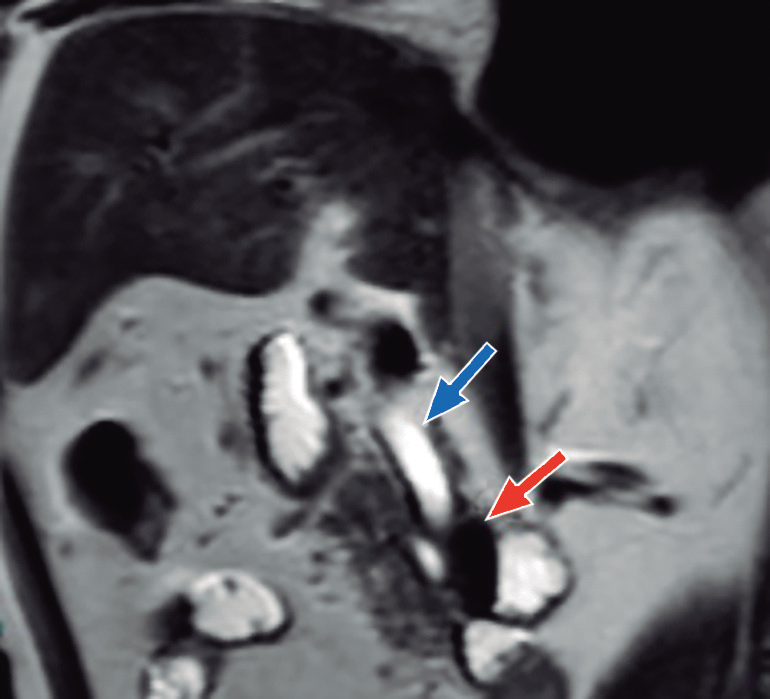

Paciente varón de 82 años, admitido en el servicio de emergencias del hospital, con un tiempo de enfermedad de dos semanas de evolución, caracterizado por dolor abdominal en el cuadrante superior derecho (CSD), fiebre e ictericia en escleras. En la exploración física se destacó la presencia de ictericia en escleras y la presencia de dolor a la palpación en CSD, con signo de Murphy negativo. Los análisis de laboratorio mostraron: recuento de leucocitos 18.7x109/L con 8% de abastonados, proteína C reactiva (PCR) 6,54 mg/dl, bilirrubina total 4,74mg/dl (bilirrubina directa 2,48mg/dl), TGO 382 U/L, TGP 377 U/L, fosfatasa alcalina 167 U/L, gamma-glutamil-transpeptidasa 1044 U/L y albúmina 2,7g/dl. La CPRM reveló una dilatación del conducto biliar común y del conducto pancreático principal a nivel de la cabeza del páncreas, sin evidencia de lesiones, y un divertículo de 23 x 21 mm a nivel de la segunda porción duodenal. No se observó dilatación de la vía biliar intrahepática ni evidencia de litos en la vía biliar o en la vesícula biliar (Figura 1).